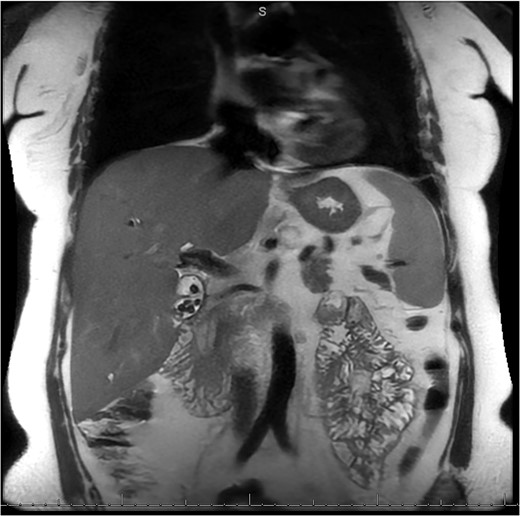

A 49-year-old female with a history of ADPKD and multiple liver cysts, 13-months status post subtotal cholecystectomy, endoscopic retrograde cholangiopancreatography with biliary sphincterotomy and balloon stone extraction, presented to the emergency department with fever and a 4-day history of discomfort in the right upper quadrant. At the time of the initial cholecystectomy, total cholecystectomy could not be performed due to extensive adhesions, and subtotal cholecystectomy with complete evacuation of the stones was done instead. Magnetic resonance cholangiopancreatography (MRCP) done at that time showed a dilated common bile duct (CBD) to 1.5 cm, intra and extrahepatic biliary dilatation, multiple liver cysts measuring up to 2 cm, and multiple stones in the CBD, including at the level of the ampulla (Fig. 1). Computerized tomography scan at the time of the second admission showed acute cholecystitis and she had mildly elevated transaminases, but there was no evidence of cholestasis or pancreatitis. MRCP showed minor proximal intrahepatic biliary dilation and cholelithiasis but no duct calculi (Figs 2–4). A laparoscopic cholecystectomy was attempted with extensive adhesiolysis between the gallbladder and surrounding omentum and mesocolon, but the cystic duct could not be isolated, and ultimately the cased was converted to open. While removing the gallbladder in a top-down fashion, a small bile leak was identified right at the closed end of the gallbladder remnant, where the bile duct was adhered to the gallbladder wall. Intraoperative cholangiogram was obtained through a small perforation in a right posterior bile duct at the site of attachment, which showed right posterior, right anterior and left hepatic ducts of equal size converged at a trifurcation (Fig. 5). The duct was repaired over a T-tube and observed throughout the rest of the case and no bile leak was identified. The gallbladder was opened along its lateral edge, revealing a hugely dilated cystic duct with ~10 to 12 marble-sized stones packed within the gallbladder remnant and cystic duct down to the juncture with the common bile duct. All the stones were removed and the safe portion of the gallbladder remnant was resected leaving the side attached to the bile duct in situ due to the Mirizzi anatomical variant. The cystic duct was oversewn along with the remnant of the gallbladder wall. Pathology showed acute-on-chronic cholecystitis with cholelithiasis. Repeat MRCP showed no retained stones in the biliary tree. The recovery course was unremarkable.

MRI/MRCP from second hospitalization demonstrating CBD of 1.1 cm.